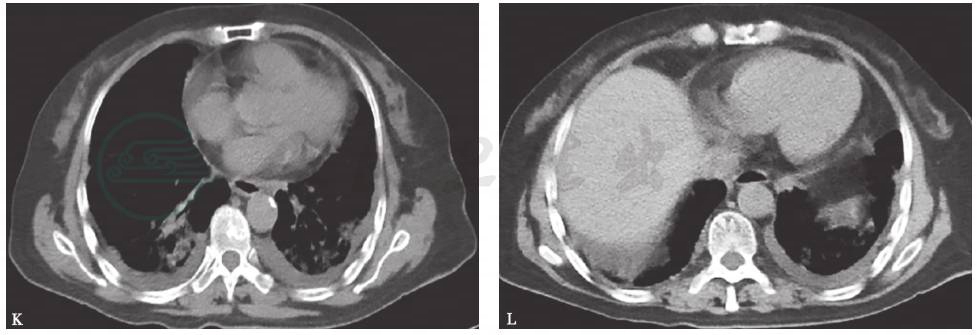

胸部CT:双肺弥漫间质性病变伴多发小结节(图1)。2个月后,随着病程延长,原有结节样病灶增多,病灶融合,形成磨玻璃及实变影,并出现双侧胸腔积液和少量心包积液(图2)。

图1 胸部CT表现(2014-03-05)

图2 胸部CT表现(2014-05-22)